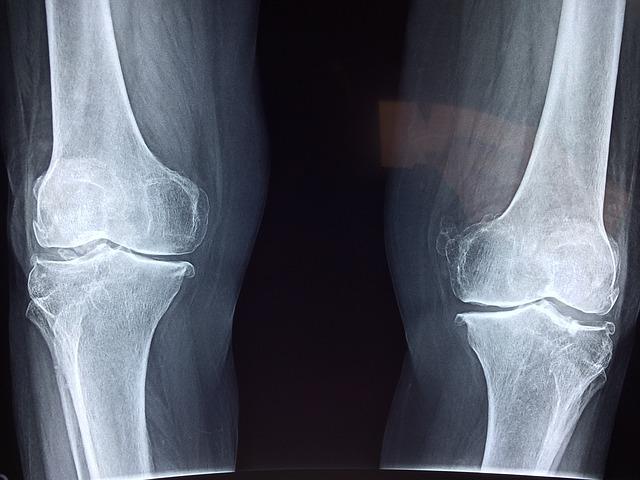

골절 위험 증가 만성피로 증가

비타민D는 대부분 뼈에 영향을 주기 때문에 부족한 경우 골다공증, 골연화증 등의 질병이 발생하고, 근육화와 근육경련 등 근육에도 영향을 끼치게 됩니다.